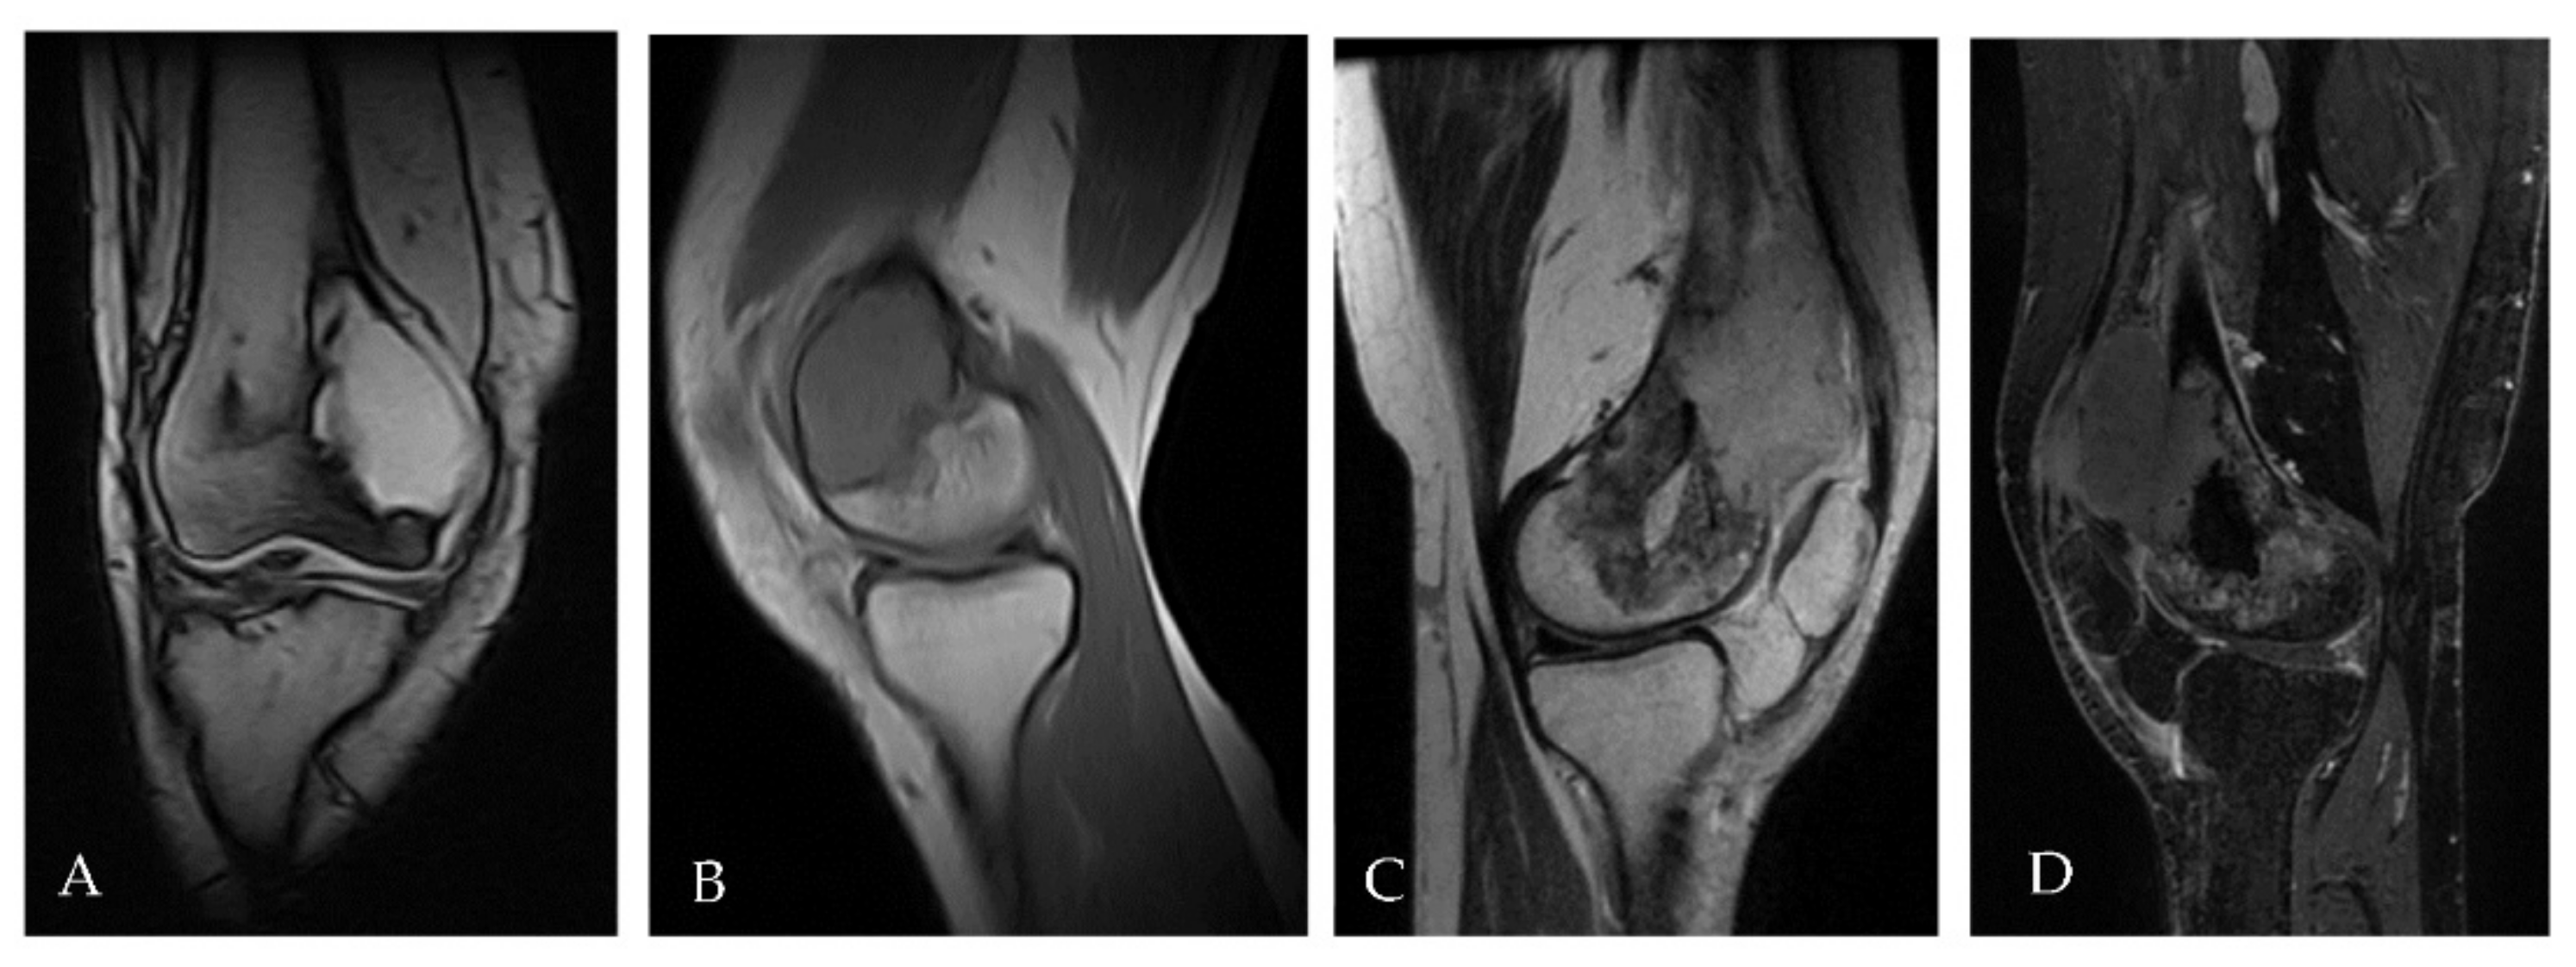

2.2. Patient 2

| Pt 2 | 48 | M | 0 | 16 November | Right tibia | Curettage and bone grafts | 20 October | Neoadj denosumab (6 cycles) | 21 February Extraarticular resection: malignant transformation of GCTB | EURO BOSS | NED | - | FU 21 December | 51 | 64 | 13 |